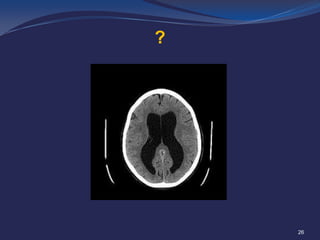

Non contrast CT of the brain demonstrates marked hydrocephalus involving

the lateral and third ventricles but sparing the fourth ventricle. .